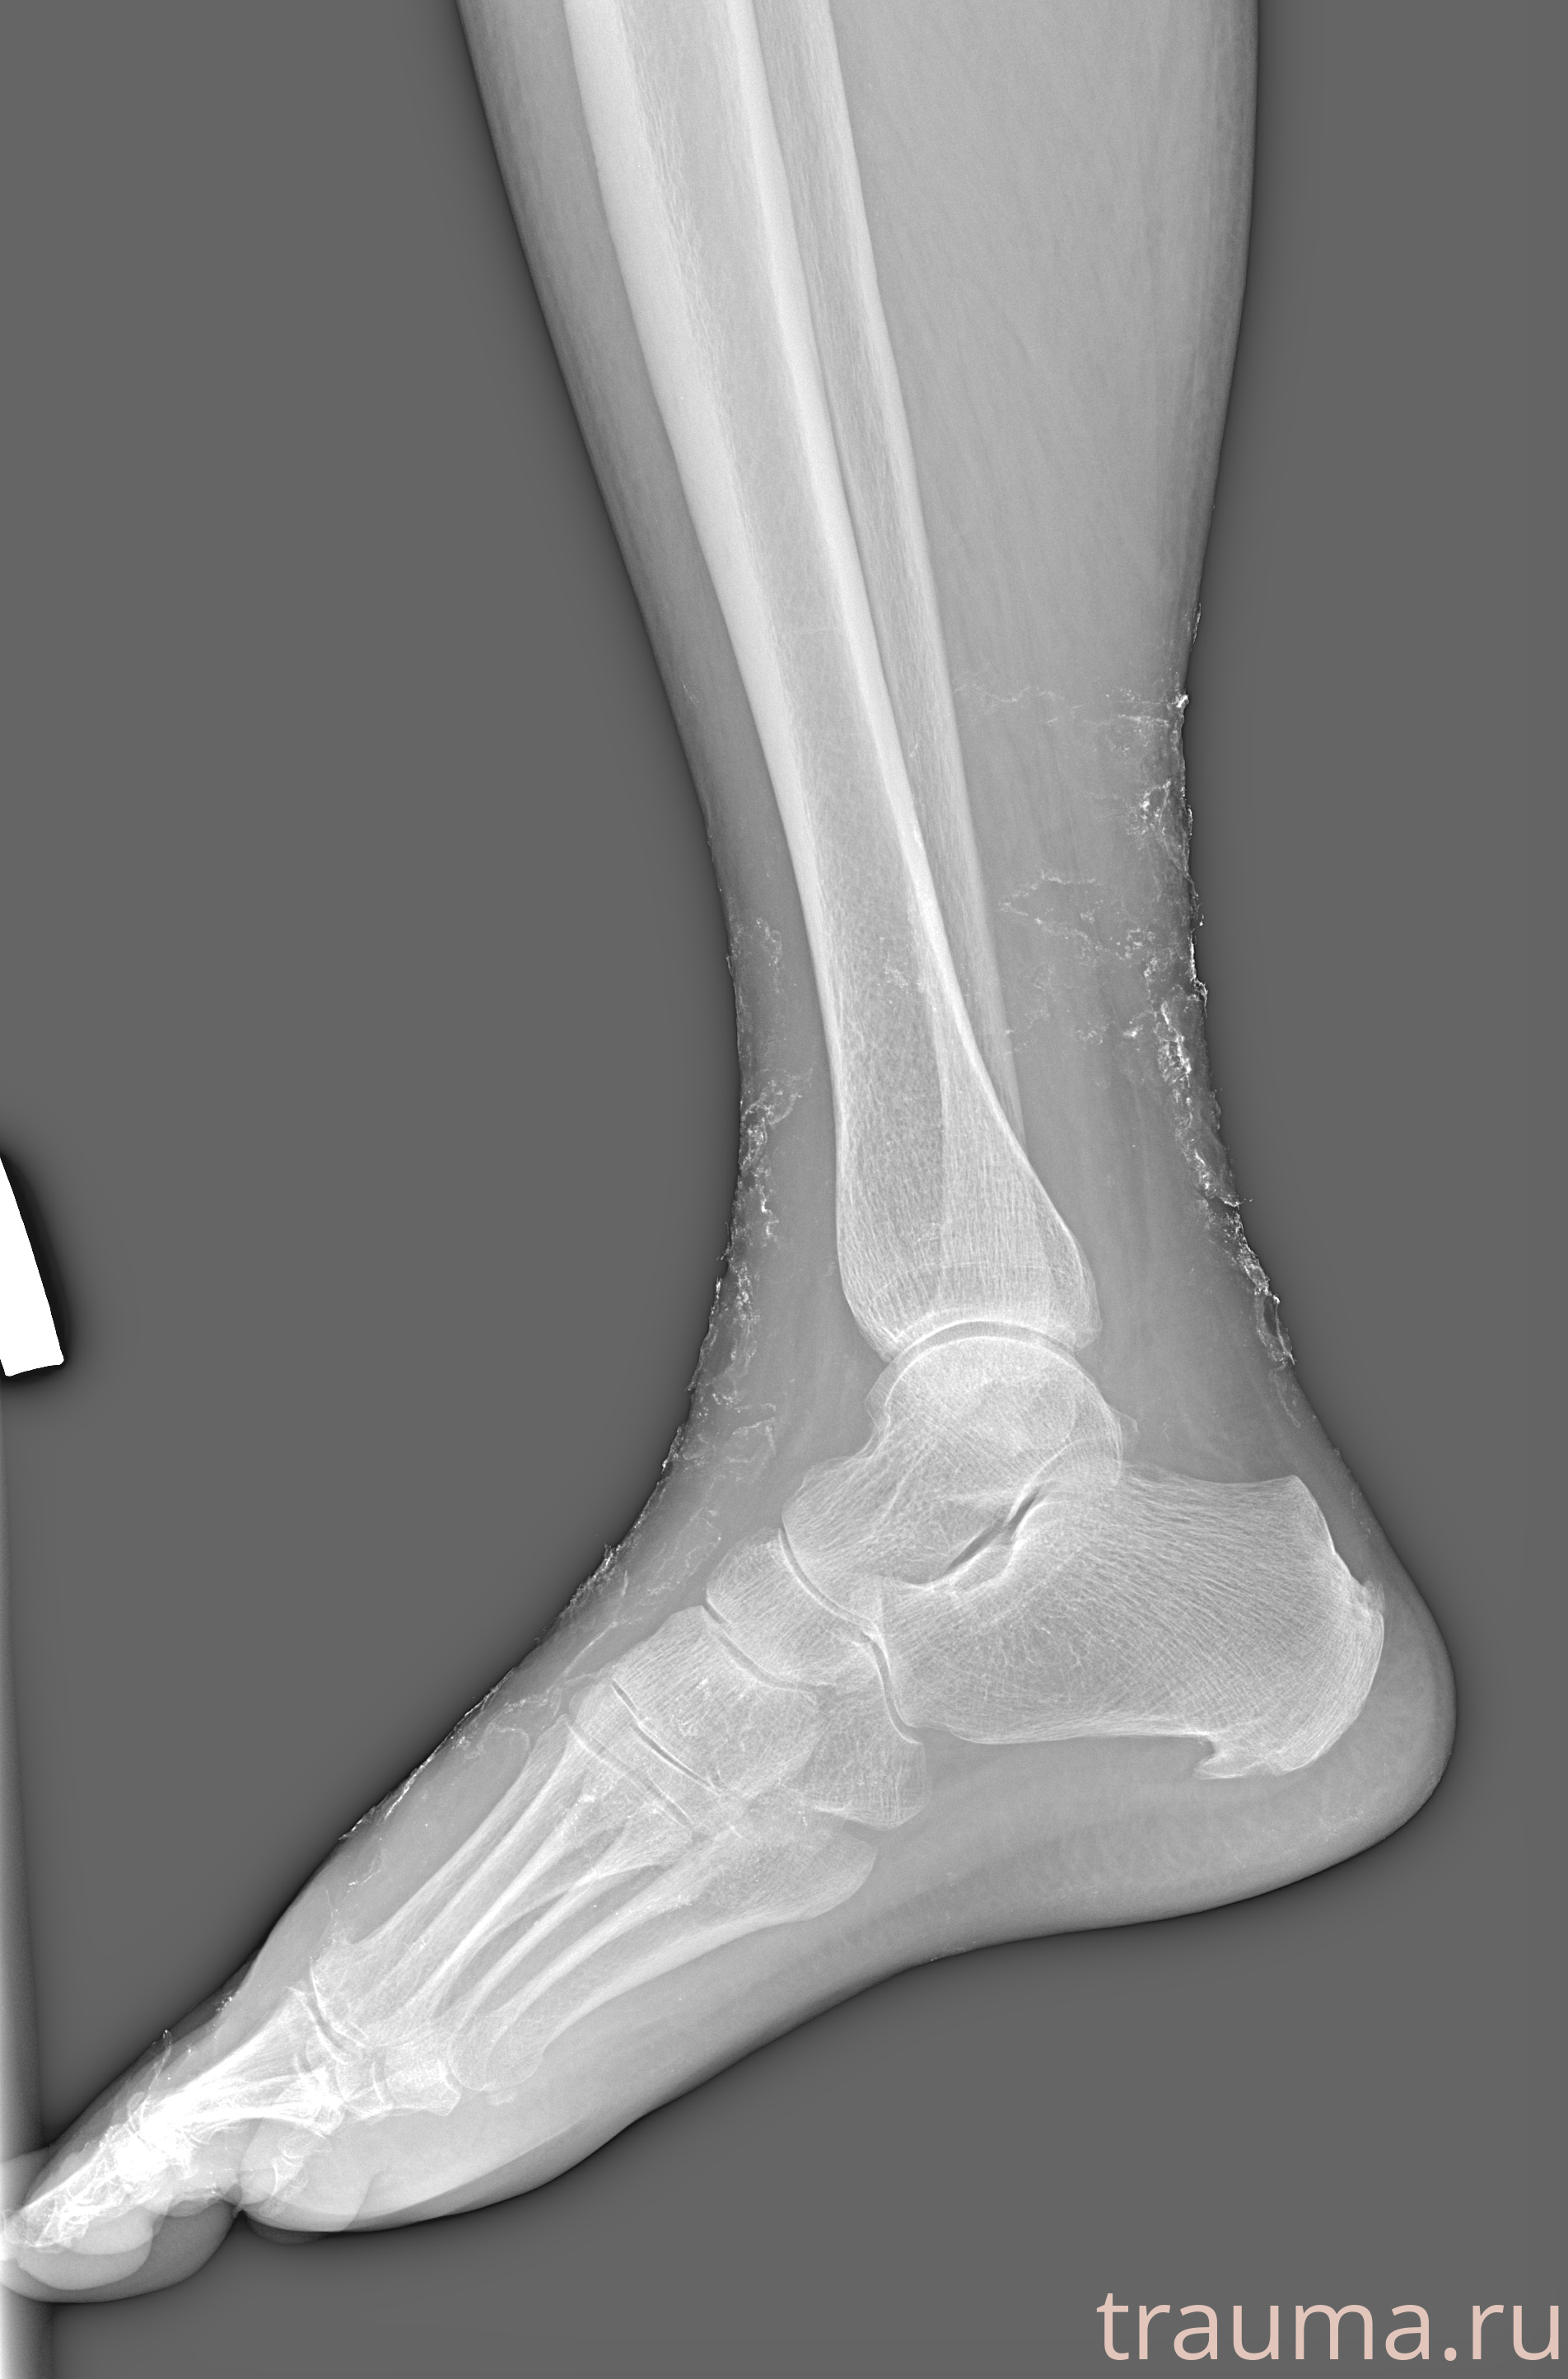

Рентген на дому: по вашему адресу приезжает врач-рентгенолог, травматолог-ортопед с мобильным рентгеновским аппаратом, проводит диагностику травмы или заболевания, делает необходимые рентгенограммы, дает рекомендации по дальнейшему лечению. Получить качественные снимки в домашних условиях возможно благодаря уникальной методике, разработанной МосРентген Центром для института  Склифосовского